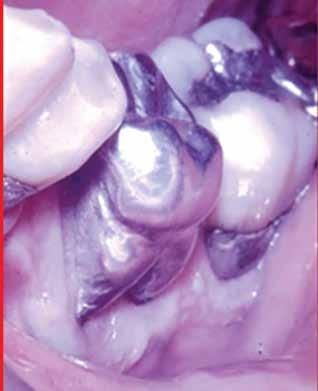

MarchApril 2026 ISSUU by Florida Dental Association - Issuu